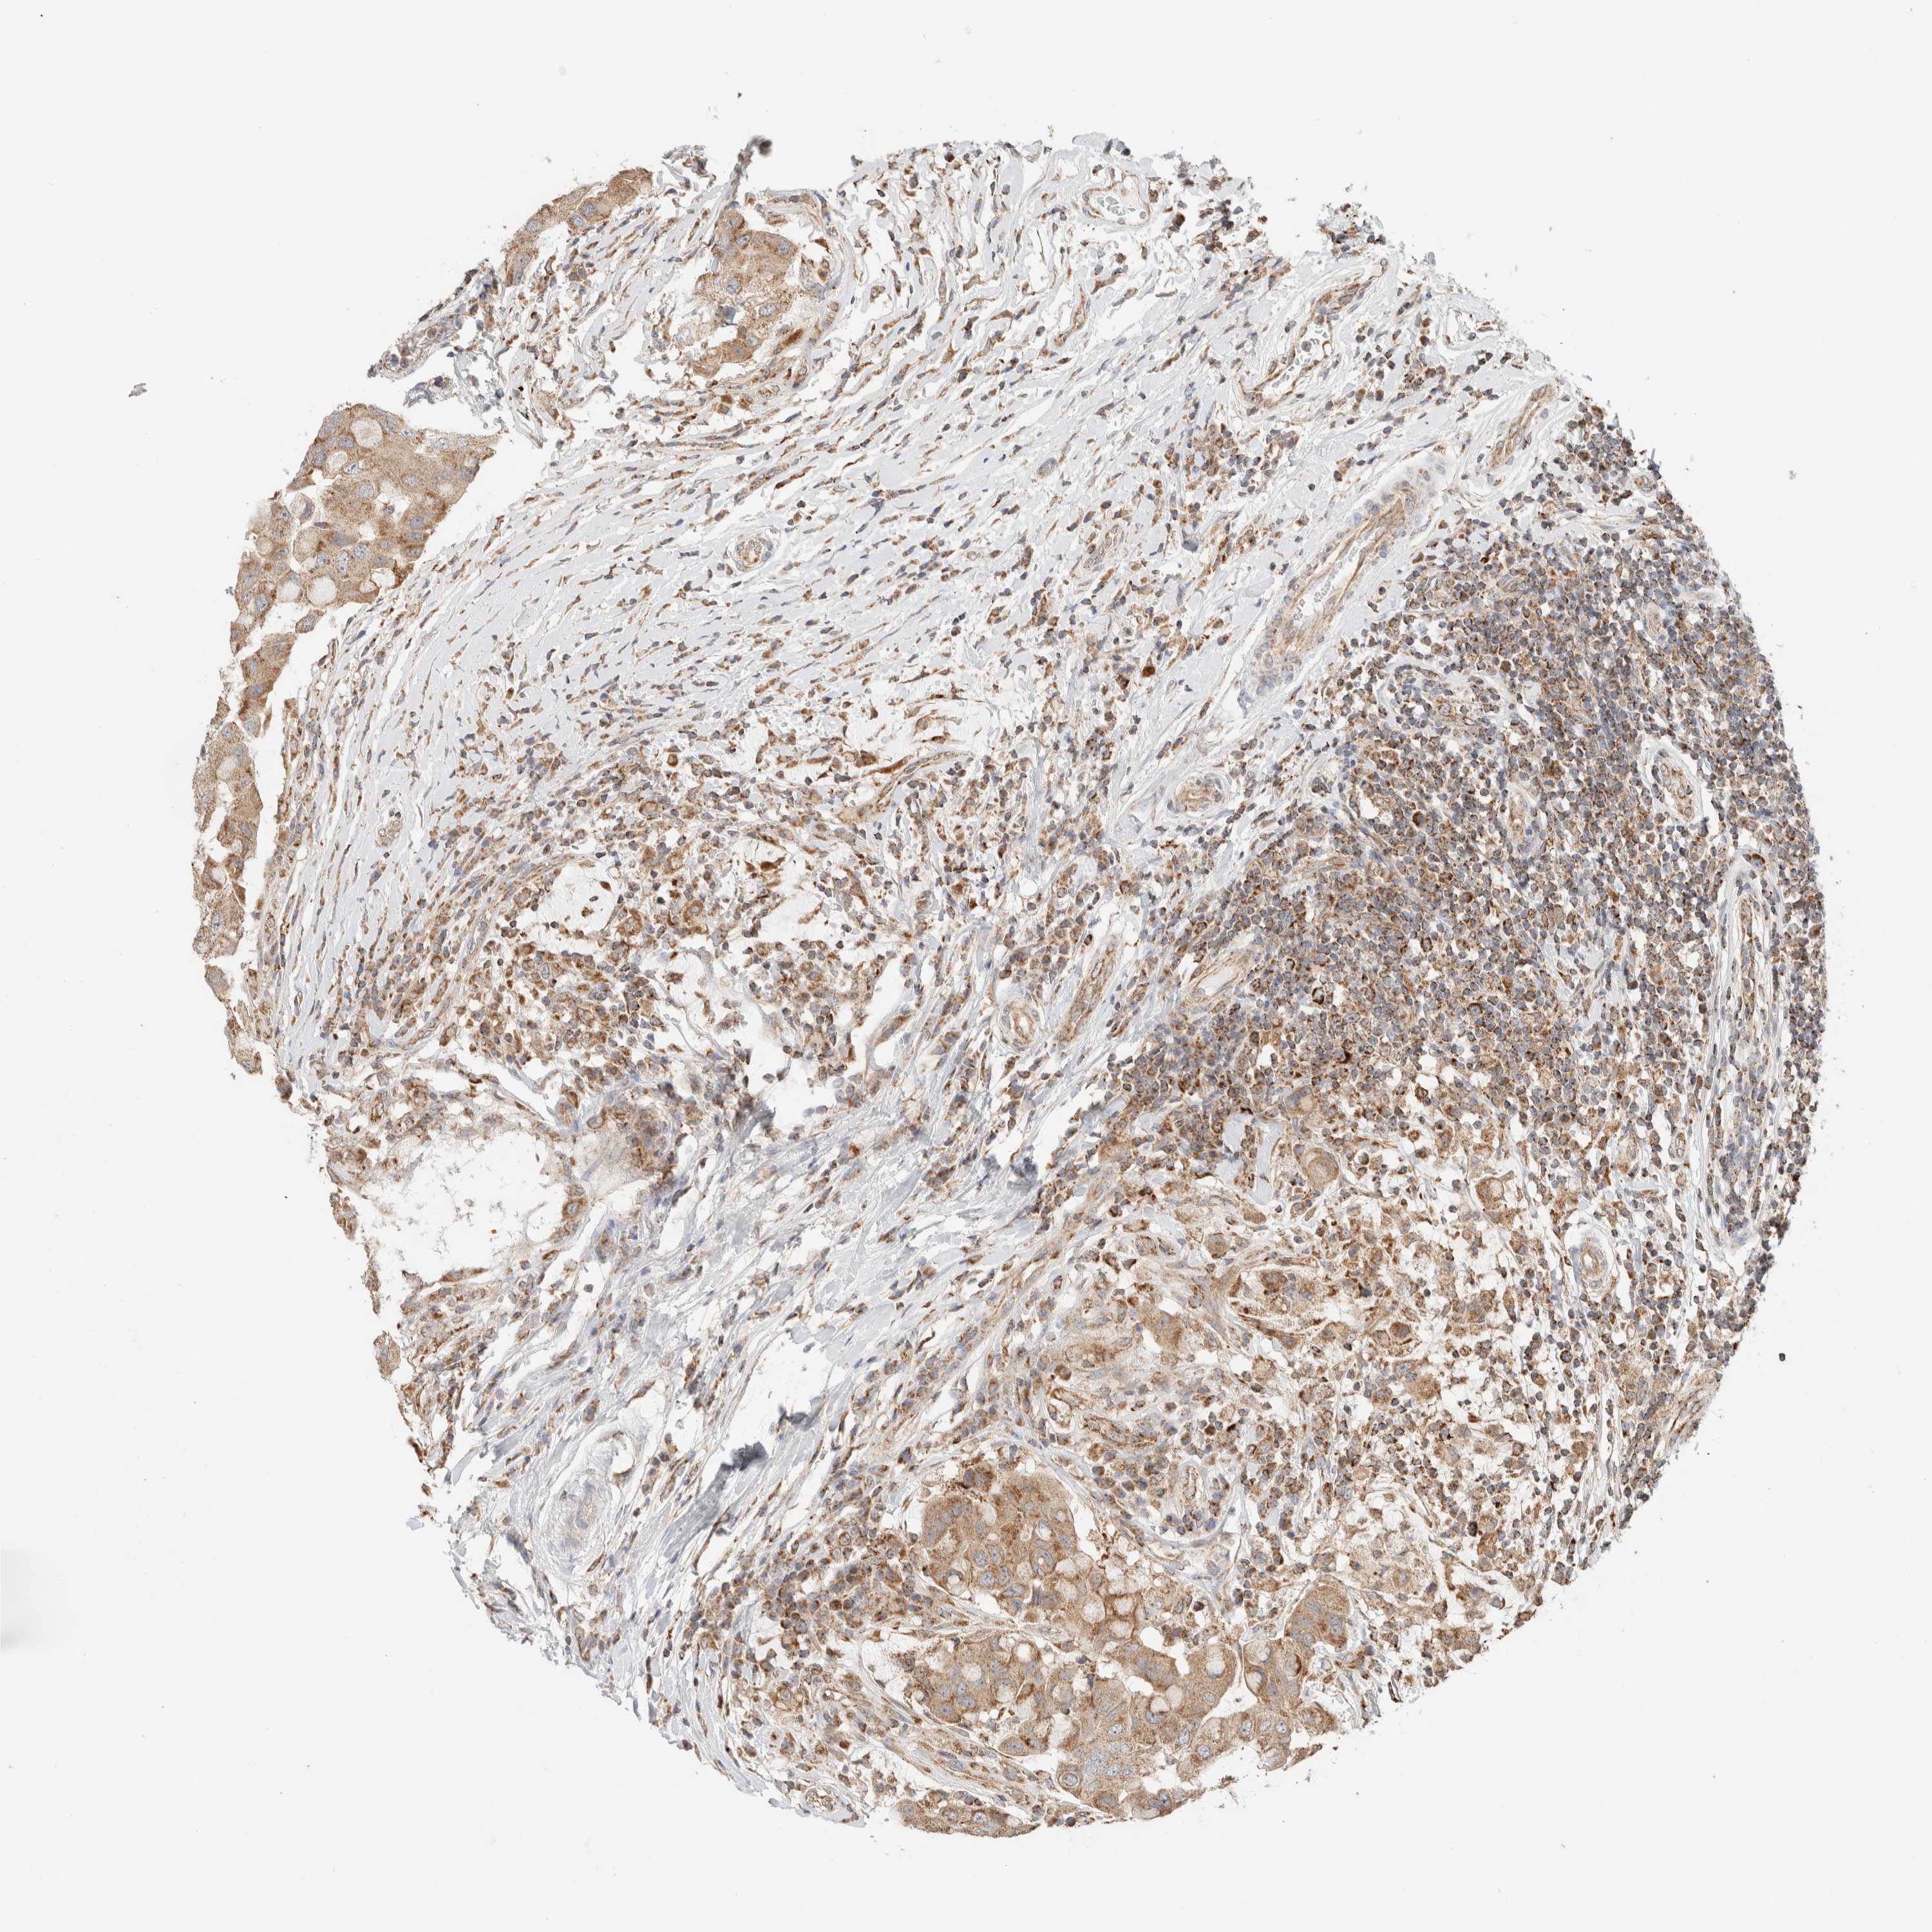

BRCA TCGA BRCA VALIDATION PROTEIN EXPRESSION

ANTIBODIES

AND

VALIDATION